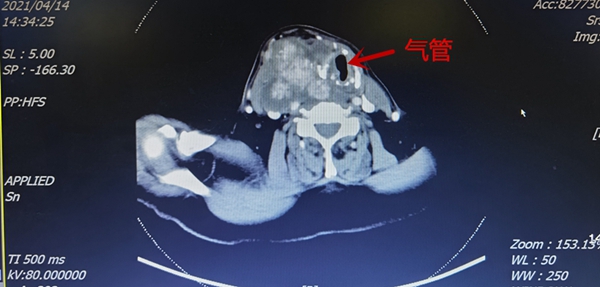

八十岁的王奶奶三年前发现自己颈部有个3公分大小的包块,在外院就诊后考虑年事已高,未进行安排手术治疗。随后几年颈部肿物逐渐增大至已影响正常呼吸,尤其夜间睡觉时出现憋喘症状,家人心急如焚,辗转多家医院求助,均因各种原因未能进行有效治疗,后慕名来我院找到普外科曹罡教授,在为其完善颈部超声后,考虑肿瘤符合甲状腺来源,予以收住入院。入院后经完善一系列细致全面的检查,颈部增强CT考虑“肿瘤严重压迫气管,气管最狭窄处宽约5mm,并且与颈部血管关系紧密”;喉镜提示患侧喉返神经麻痹;气管钡透提示造影剂呛入气管,提示喉上神经功能受损。气管镜提示气管可疑受侵犯。穿刺活检提示甲状腺乳头状癌。目前患者气管严重偏移狭窄,肿瘤与周围血管、气管、食管、神经可能存在的侵犯为手术带来了巨大的难度:气管狭窄难以完成麻醉插管,诱导麻醉过程中可能窒息;长期压迫气管可能造成气管软化,术后塌陷窒息;对气管的侵润可能需要切除部分气管并重建气道;对喉返神经的侵犯需要术中严格保全健侧喉返神经功能,否侧患者术后将会出现窒息;肿瘤侵犯于颈内静脉与颈内动脉关系密切,切除肿瘤后还要能够保留血管功能,保护大脑的血液供应及回流。